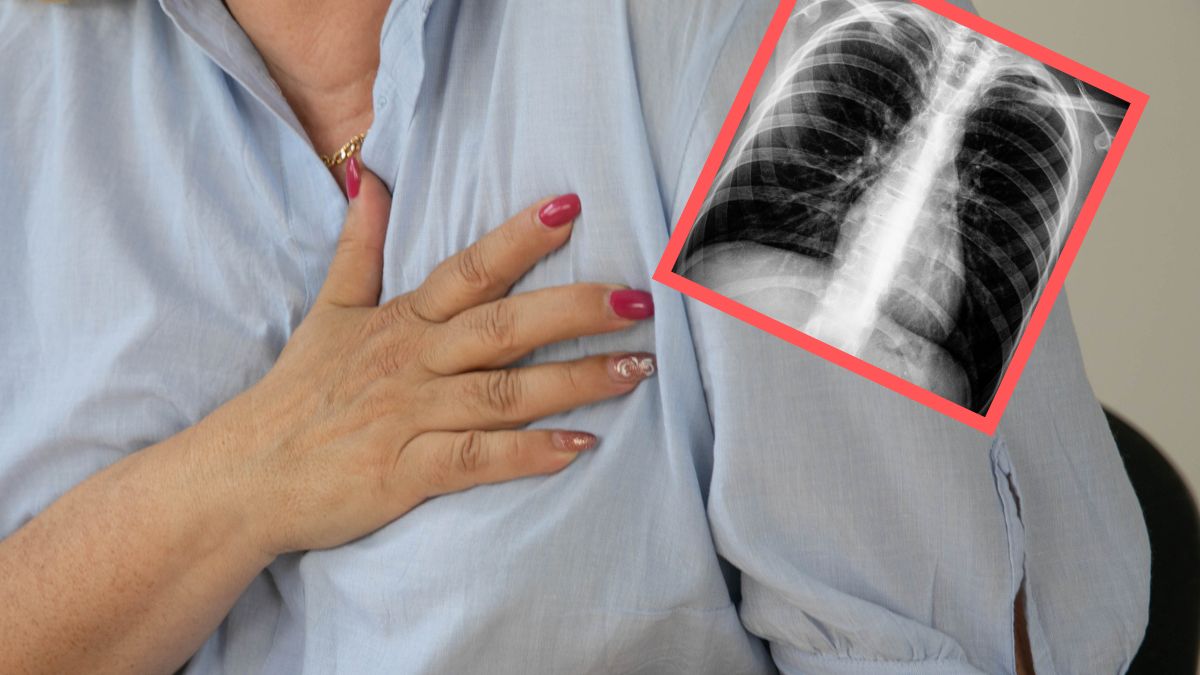

Rak płuc przez długi czas może rozwijać się w organizmie bez wyraźnych objawów, dlatego często wykrywany jest dopiero w zaawansowanym stadium. Choć kaszel, duszność i ból w klatce piersiowej to klasyczne symptomy kojarzone z tą chorobą, warto wiedzieć, że rak płuc może dawać również mniej oczywiste sygnały.

Kluczowe znaczenie w walce z rakiem płuca ma szybka diagnostyka. Wczesne wykrycie nowotworu zwiększa szansę na skuteczne leczenie i znacząco poprawia rokowania pacjenta. Dlatego tak ważne jest, aby nie ignorować niepokojących objawów, takich jak przewlekły kaszel, duszności czy ból w klatce piersiowej. Choć są to jedne z najczęstszych sygnałów choroby, są też inne - mniej oczywiste, o których warto wiedzieć dla swojego zdrowia.

Jakich objawów raka płuca można się jeszcze spodziewać? Do mniej charakterystycznych symptomów zalicza się:

• ból barku i szyi - guz Pancoasta to szczególna postać raka płuc, która rozwija się w górnej części płuca i często nie wywołuje typowych objawów, takich jak kaszel czy duszność; zamiast tego może naciekać okoliczne struktury – nerwy, naczynia krwionośne, kręgosłup czy żebra – powodując ból barku i szyi,

• obrzęk twarzy i szyi - pojawia się, gdy guz uciska duże naczynie żylne odpowiedzialne za odpływ krwi z górnej części ciała. To objaw, który powinien skłonić do pilnej diagnostyki,

• palce pałeczkowate - powiększenie i zaokrąglenie opuszek palców oraz paznokci, które mogą wyglądać na wypukłe i błyszczące wskutek zaburzeń krążenia w końcówkach palców,

• zaburzenia neurologiczne - osłabienie kończyn, zawroty głowy, drętwienie lub utrata równowagi mogą być wynikiem nacisku guza na struktury nerwowe lub obecności przerzutów do mózgu,

• spadek masy ciała i zmęczenie - nagła utrata wagi i przewlekłe zmęczenie, które nie mijają mimo odpoczynku, mogą być jednym z pierwszych sygnałów rozwijającej się choroby nowotworowej.

Rak płuca nie zawsze objawia się w oczywisty sposób. Nieoczywiste symptomy – takie jak ból barku, zmiany w wyglądzie palców czy przewlekłe zmęczenie – mogą być łatwo pomylone z innymi dolegliwościami. Właśnie dlatego tak ważna jest czujność wobec sygnałów wysyłanych przez organizm oraz szybka reakcja. Regularne kontrole, unikanie czynników ryzyka i zgłaszanie nawet drobnych, ale niepokojących objawów lekarzowi mogą znacząco zwiększyć szansę na wczesne wykrycie choroby i skuteczne leczenie. Zdrowie zaczyna się od świadomości – warto o nie zadbać, zanim pojawi się realne zagrożenie.